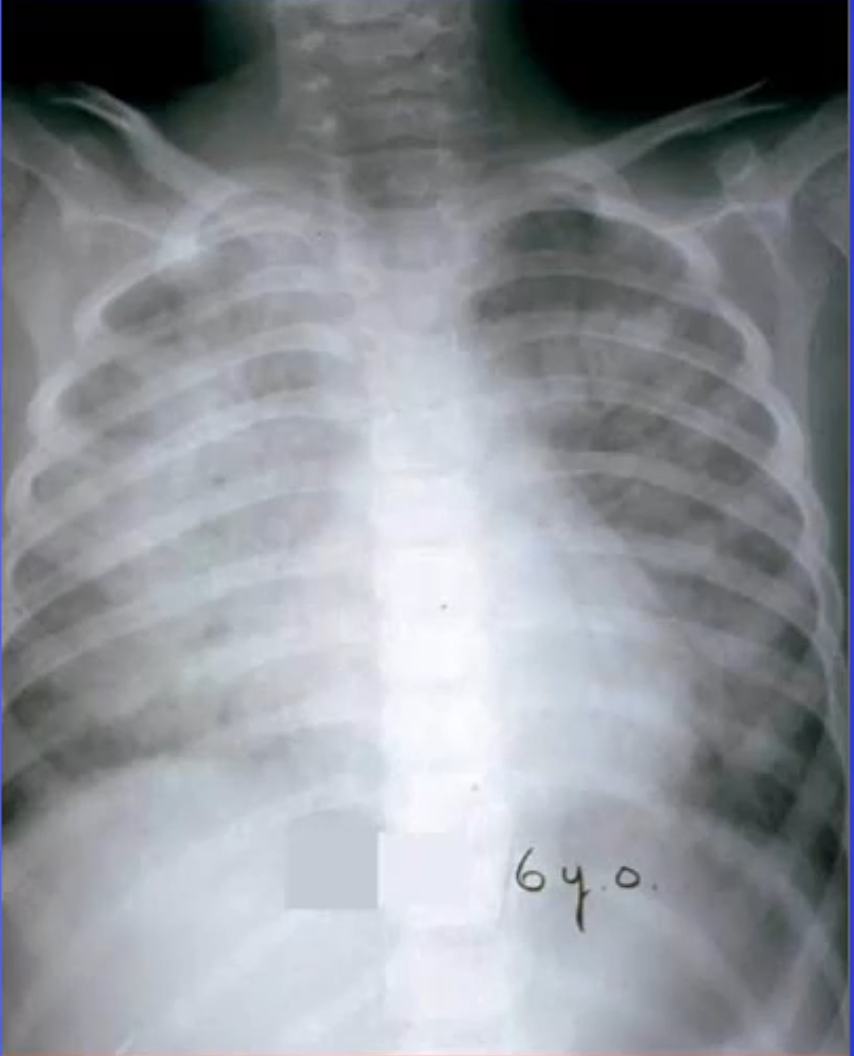

Complications